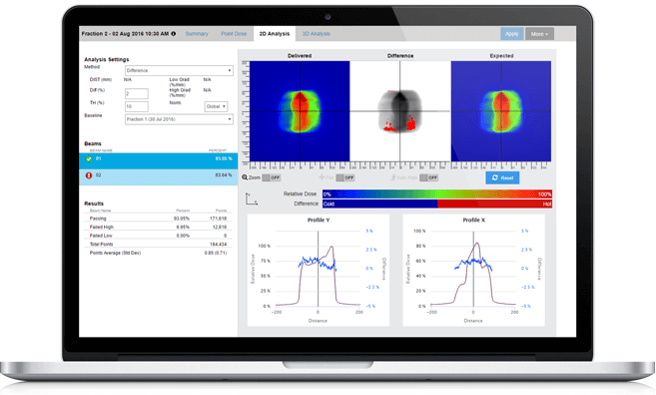

Iterative Reconstruction

Iterative reconstruction refers to iterative algorithms used to reconstruct 2D and 3D images in certain imaging techniques. For example, in computed tomography, an image must be reconstructed from projections of an object. More recently, a much more complex iterative reconstruction algorithm has become available called fully-model-based iterative reconstruction. The implementation of iterative reconstruction can be an important component of overall CT radiation dose reduction – Imaging Wisely – without compromising diagnostic content in CT studies.